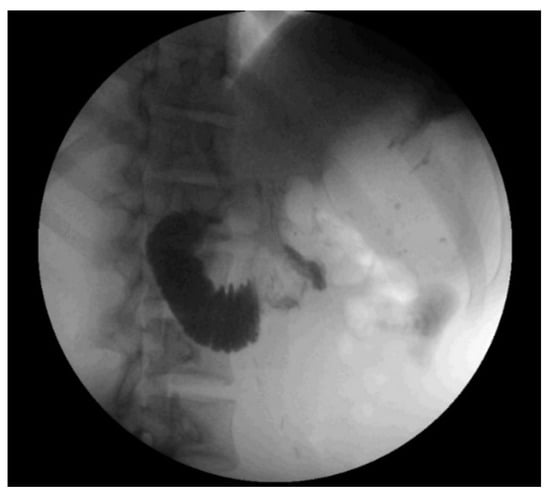

The patient underwent resection of the 11.1 kg, 70 cm mass without en bloc visceral resection; surgical margins were negative with no capsular disruption or intra-operative tumor spillage. It is worth noting that the duodenum was visualized crossing the midline, and the ascending, transverse, and descending colons were in their normal anatomic positions, excluding pre-existing malrotation. At the conclusion of the resection, he was noted to have near-complete absence of lipomatous tissue in his retroperitoneum. Post-operatively, he was persistently intolerant of diet advancement; despite apparently successful attempts at nasogastric decompression with evidence of bowel function, he demonstrated persistent bilious emesis with a benign abdominal exam. An upper gastrointestinal series revealed abrupt cutoff of contrast in the mid-duodenum, with significantly delayed transit of contrast distally (Figure 2). Abdominal CT demonstrated duodenal compression by the SMA with a reduced aortomesenteric distance of 8 mm, diagnostic of SMA syndrome (Figure 3). A nasojejunal feeding tube was placed fluoroscopically; the patient quickly tolerated goal tube feeds and began gaining weight. He remained nil per os for 4 weeks after discharge with continued weight gain, before slowly resuming oral intake. The patient’s intolerance to oral intake has resolved; he is now independent of tube feedings and has returned to near the 50th weight percentile for his age and height.

Figure 2. Representative image from upper gastrointestinal series showing abrupt cutoff of oral contrast in the mid-transverse duodenum, suggestive of superior mesenteric artery syndrome.